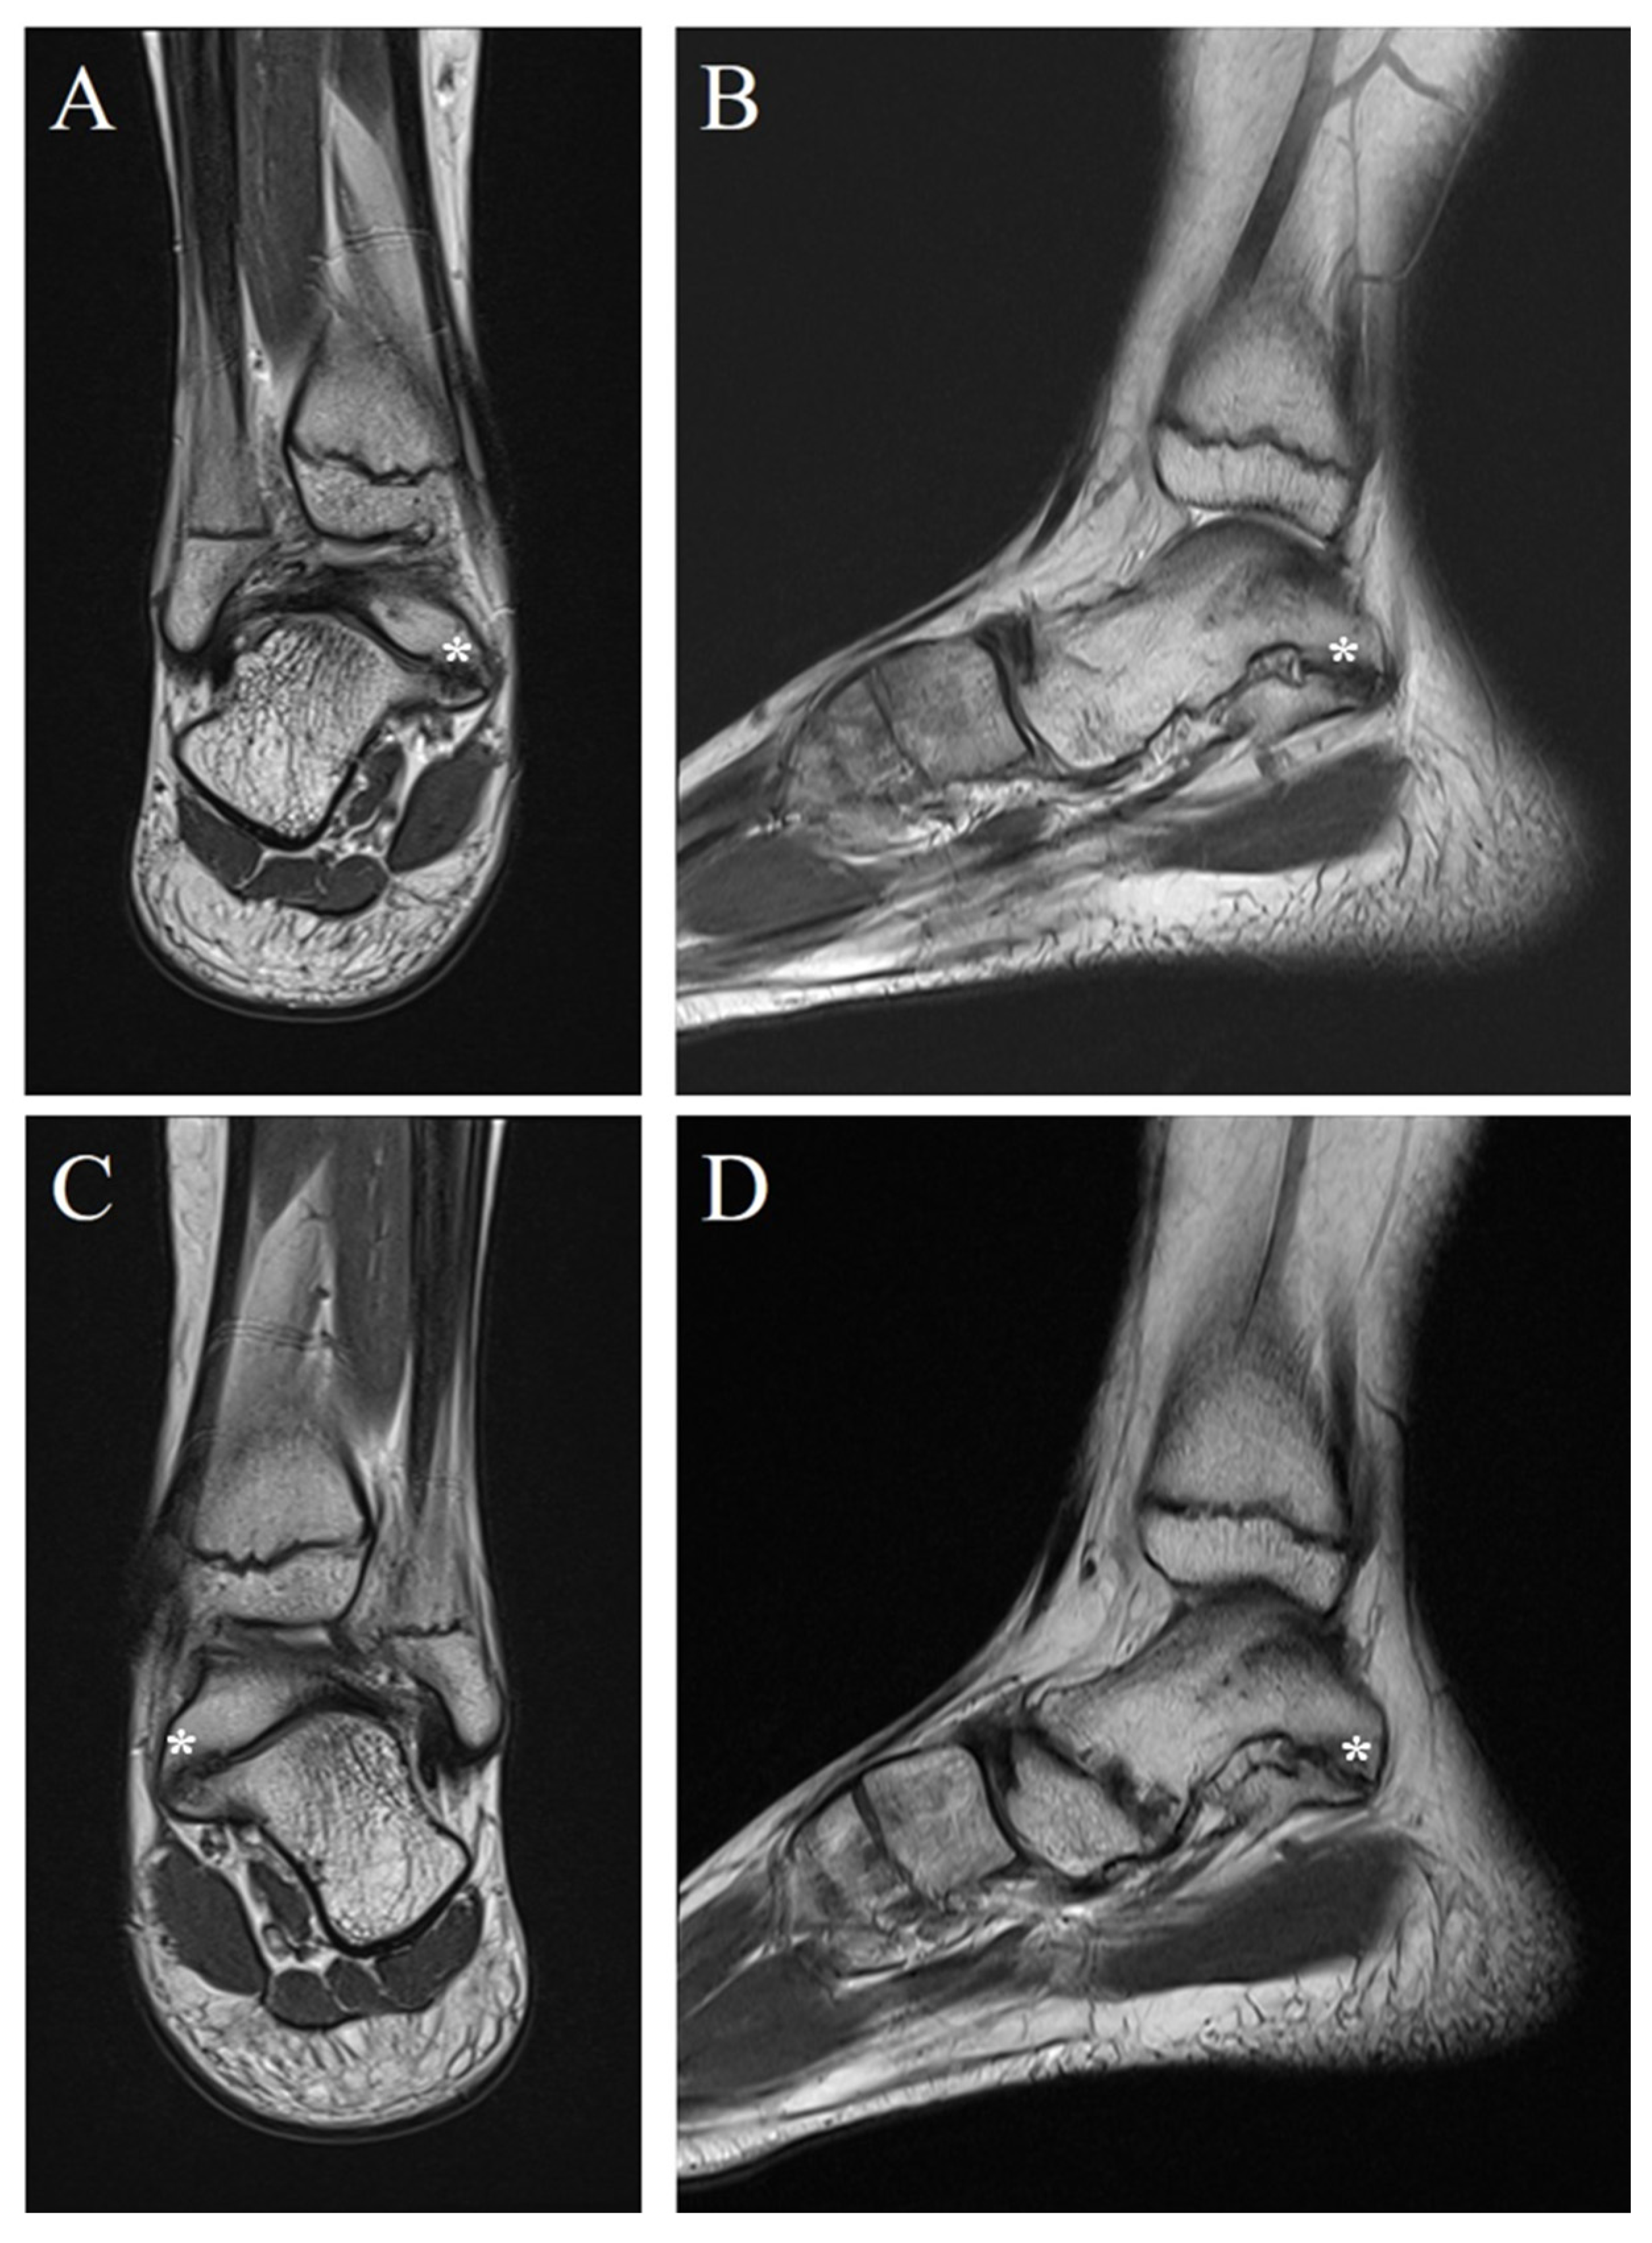

Bilateral Multiple Tarsal Coalitions (Talonavicular and Talocalcaneal Coalitions) with Recurrent Ankle Sprain in an Adolescent

2. Case Report